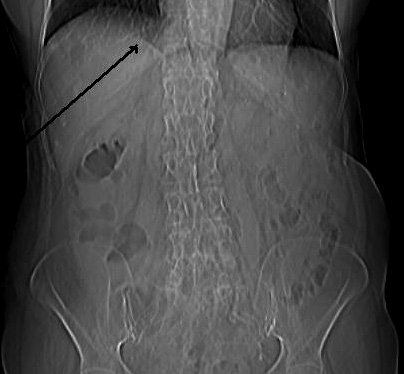

La CT scanner de l'abdomen du

tube digestif et des voies biliaire :

La Tomodensitometrie computerisation

( CT scanner ) simple se base sur la

balayage d'une faisceau de rayon x sur le patient en plusieures de angles inclinees sur une

meme plan de coupe . Les signales a receuillir par detecteur de rayon

X a

cote opposee du faisceau , seraient traites en informatique

numerique a aide d'outils mathematiques ( algorithmes) ce

qui permettre de recontruire en image un coupe anatomique .

Cette methode est plus couteuse que echographie mais est

l'examen de deuxieme intention pour exploration de la

pathologie du foie , des voies biliaires et de pancreas

. Sa resolution et image de receuillir etre bien et sa champ

de visuelle est plus large que echographie .Ce qui ainsi

peut utilise de recherche de adenopathie et de extention

locale ou metastasique de cancer de voie biliaire .

...Recontruction multiplanaire

et resolution spaciale en trois plans pour explorer et les

coupes doient fine de moins 3mm a low dose . L'etude du grele par CT scanner necessite un opacification

des anses intestinales par produit de contrast a ingestion

simple par la bouche : enterographie avec tomodensitometrie

ou intillation par sondage : enteroclyse avec scanner .

Diagnostic des pathologies du grele se met sur etude de

epaisseur de la paroi du grele ou de defaut de remplissage de

la lumiere intestinale .

L'indication de CT scanner digestive

sont vastes : ils sont necessaire pour un grand nombre de

pathologies digestive , les lesions inflamatoires , tumorales ,

traumatiques , vasculaires ou mecaniques. Et encore a aide du CT

scanner tous les organes pleines abdominaux , les vaisseaux

, les aires ganglionaires et la graisse intra abdominale

sont en meme de explore . La tomodensitometrie helicoidale : combinant

la rotation continue des detecteurs du tube de rayon X avec

un deplacement longitudinal du patient , ce qui permet

acquisition en quelques seconds d'un volume de lesion .